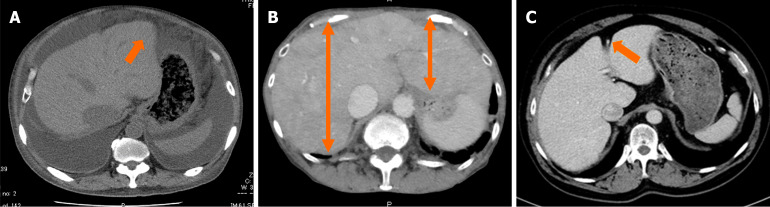

Methods: We retrospectively analyzed 179 chronic HF patients who underwent echocardiography and CT within one year. Right HF severity was classified into three grades. Liver CT images at the paraumbilical vein level were used to develop a ResNet-based machine learning model to predict tricuspid regurgitation (TR) severity. Model accuracy was compared with that of six gastroenterology and four radiology experts.